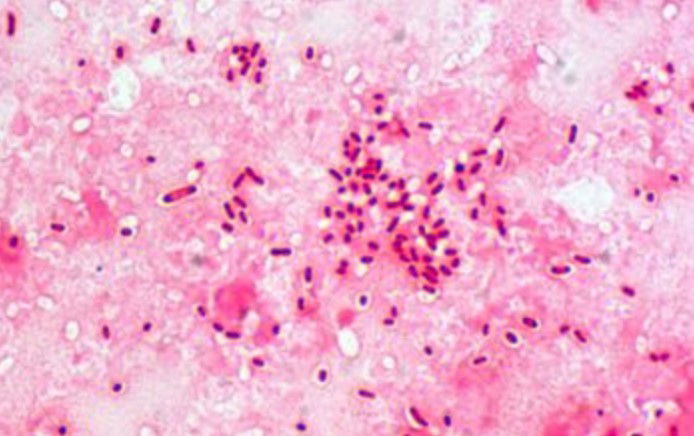

Il Citrobacter, il batterio che avrebbe causato la morte di quattro bambini sarebbe stato annidato in un rubinetto dell’acqua utilizzata dal personale della Terapia intensiva neonatale dell’Ospedale della Donna e del Bambino di Borgo Trento a Verona

Il Citrobacter, il batterio che avrebbe causato la morte di quattro bambini sarebbe stato annidato in un rubinetto dell’acqua utilizzata dal personale della Terapia intensiva neonatale dell’Ospedale della Donna e del Bambino di Borgo Trento a Verona il Citrobacter. Il reparto è stato chiuso.

La storia del Citrobacter era quella che Zaia illustrava in conferenza stampa mentre Salvini gustava ciliegie: il batterio tra la fine del 2018 e quest’anno ha ucciso quattro neonati. E forse sarebbe bastato evitare di usare l’acqua di rubinetto per i bambini invece dell’acqua sterile. É la conclusione a cui giunge la relazione di una delle due commissioni nominate dalla Regione Veneto, e di cui un’anticipazione è stata pubblicata oggi dal Corriere del Veneto. Si tratta della cosiddetta “commissione esterna”, coordinata da Vincenzo Baldo, ordinario di Igiene e Sanità pubblica all’Università di Padova. Un’altra relazione, che sarà consegnata alla Prociura della repubblica di Verona, è composta da membri interni all’amministrazione regionale.

Secondo le conclusioni della commissione esterna, il Citrobacter avrebbe colonizzato il rubinetto probabilmente a causa di un mancato o parziale rispetto delle misure d’igiene; un altro errore potrebbe essere stato di ricorrere all’acqua del rubinetto e non ad acqua sterile. I primi controlli da parte dei vertici dell’Azienda ospedaliero-universitaria di Verona erano stati avviati a gennaio poi erano stati interrotti a causa dell’emergenza Coronavirus. L’intero reparto di Ostetricia – Punto nascite, Terapia intensiva neonatale e Terapia intensiva pediatrica – è stato riaperto oggi, dopo che il 12 giugno scorso il direttore generale dell’Aou veronese, Francesco Cobello, ne aveva disposto la chiusura, procedendo alla totale sanificazione degli spazi. Zaia ha spiegato ad ANSA di aver trasmesso alla Procura la relazione: “Ho ricevuto la relazione sul caso del batterio Citrobacter all’Ospedale della Donna e del Bambino di Verona da parte della Commissione ispettiva che ho fatto attivare a suo tempo, presieduta dal Professor Baldo dell’Università di Padova. Ho dato disposizione al segretario regionale della Sanità Mantoan -prosegue- che tale relazione venga inoltrata alla Procura della Repubblica e resa disponibile per l’Azienda Ospedaliera Universitaria Integrata di Verona e per i famigliari dei bambini colpiti dal batterio, in modo che possano conoscere gli esiti fin da subito”